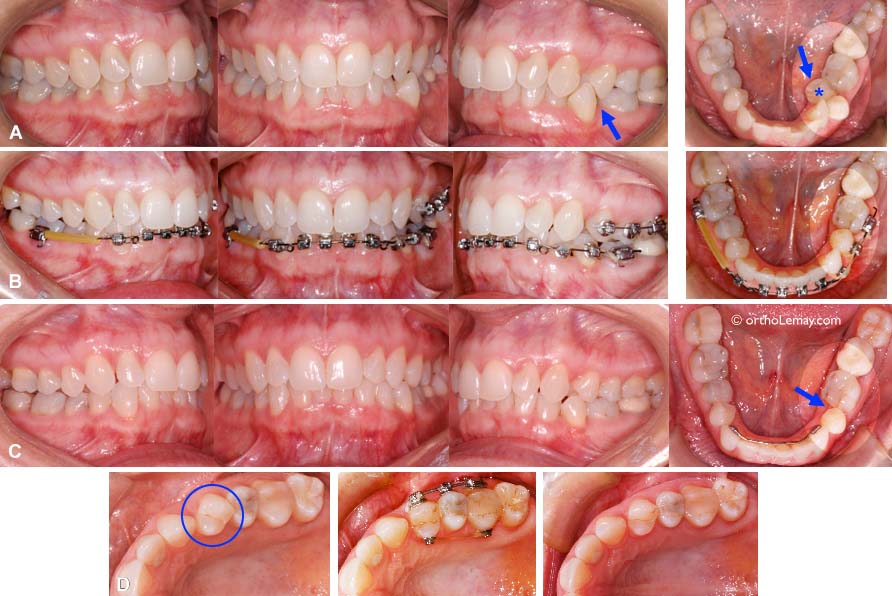

Cas 2 – Correction des incisives supérieures pour minimiser l’usure excessive des dents antérieurs

Traitement de compromis en orthodontie chez un adulte (56 ans) ayant de l’usure dentaire excessive. Voir ci-dessous pour une description détaillée de ce cas. Durée du traitement: 7 mois

(A et B) Occlusion initiale où l’on peut voir les incisives supérieures qui surplombent excessivement celles du bas et qui sont basculées vers l’arrière. La flèche indique une fistule qui draine un abcès à l’apex de la latérale droite. Le fait que cette dent soit endommagée par l’usure et qu’elle subisse des forces constantes plus fortes à cause de sa malposition ont pu contribuer à la nécrose du nerf de la dent ayant causé l’abcès dentaire. Cette dent nécessitera un traitement de canal.

(C) Vue en plongée du surplomb vertical et de la proximité des dents des deux arcades.

(D) Une vue rapprochée révèle l’usure excessive des dents. Les zones plus foncées sont la dentine de la dent qui est devenue visible après que l’émail qui la recouvre ait complètement disparu (usé).

(E) Les incisives inférieures centrales sont tellement usées qu’on peut y voir le canal pulpaire (où est le nerf de la dent) plus foncé et indiqué par les flèches. Ces dents ne sont toutefois pas douloureuses car le canal se “momifie” en fabricant de la dentine qui obstrue progressivement le canal à mesure que progresse l’usure.

(F) Vue de face, bouche ouverte; l’usure des incisives inférieures est évidente.

(G) Début du traitement avec les appareils multi-bagues fixes sur les dents supérieures.

(H) Bien que l’arcade inférieure ait plusieurs irrégularités et malpositions dentaires, elle ne fut pas traitée.

(I) Fin des corrections; les incisives supérieures ont été inclinées vers l’avant pour les “dégager” des dents inférieures et diminuer les risque d’usure future (sans toutefois le “garantir”). Elles ont aussi été légèrement “remontées” verticalement (comparez A et I). La durée du traitement fut de 7 mois.

(J) Une attelle de rétention fixe a été posée sur la surface interne des incisives.

Cas 1 – Corrections inférieures pour éliminer une dent endommagée et condamnée à l’extraction

(A) Occlusion avant le traitement ; Il y a du chevauchement sévère à l’arcade inférieure gauche causant une occlusion croisée et un endroit difficile à nettoyer pour la patiente (flèches). Le but du traitement était de corriger l’alignement inférieur gauche. Afin d’obtenir l’espace nécessaire, une prémolaire cariée a été extraite (* bleu) et des appareils multi-bagues furent posés au bas et sur quelques dents postérieures afin de corriger la rotation de la première prémolaire qui nuisait à la correction de la prémolaire inférieure (B et D).

(C) À la fin du traitement (durée de 8 mois) l’espace est fermé, les dents sont alignées et la nourriture ne reste plus emprisonnée. Les autres aspects de l’occlusion ont été modifiés le moins possible.